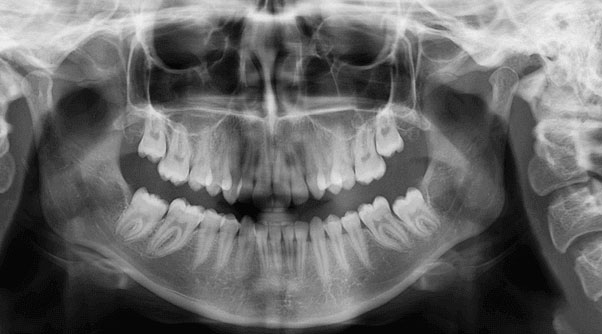

Digital OPG X-rays are a type of dental X-ray that provides a panoramic view of the upper and lower teeth, jawbones, and temporomandibular joints (TMJs). They are used to diagnose a variety of dental and jaw conditions.

Digital OPG X-rays are used to diagnose a variety of dental and jaw conditions, including:

- Impacted teeth: Impacted teeth are teeth that are trapped in the jawbone and cannot erupt into the mouth.

- Jawbone fractures: Digital OPG X-rays can be used to diagnose jawbone fractures.

- TMJ disorders: Digital OPG X-rays can be used to diagnose TMJ disorders, which are problems with the TMJs.

- Tooth decay: Digital OPG X-rays can be used to detect tooth decay.

- Periodontal disease: Digital OPG X-rays can be used to detect periodontal disease, which is an infection of the gums and supporting bone.